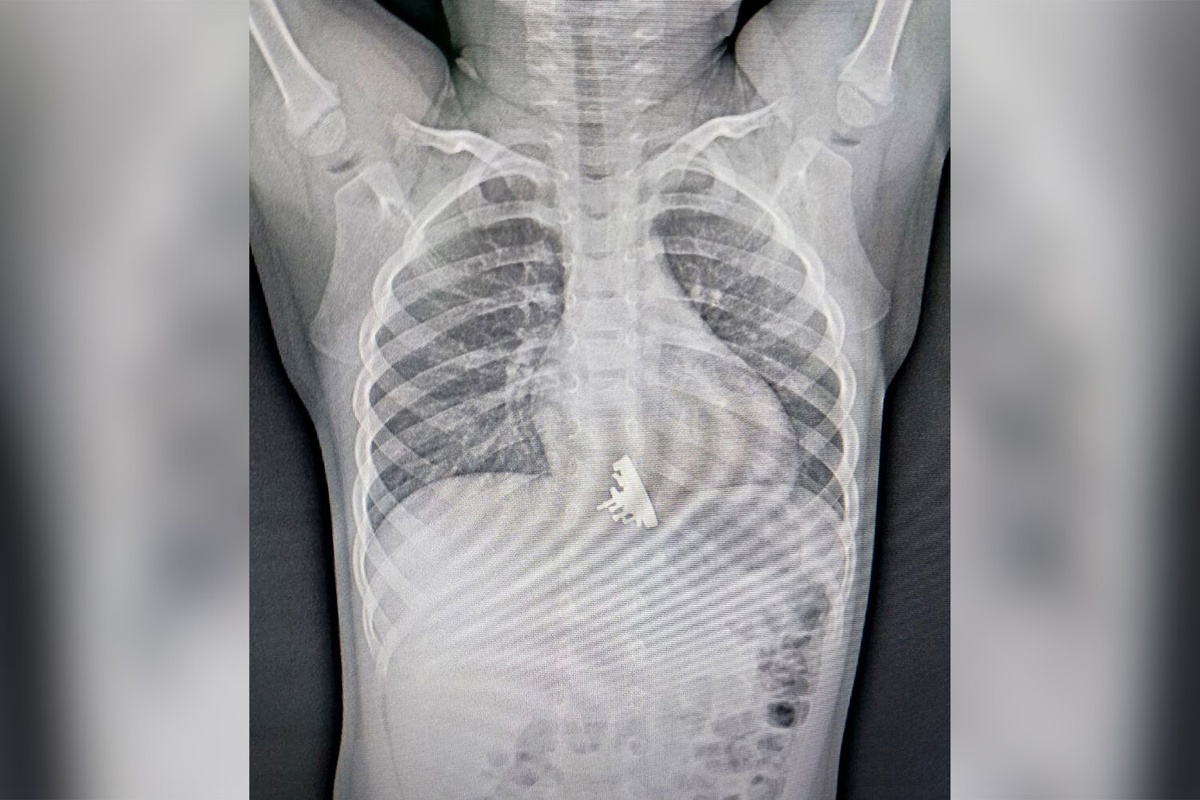

Крейсер «Аврора» достали из двухлетней девочки в Иркутске

Ребенку провели рентген, по результатам которого стало ясно, что у девочки в нижней трети пищевода находится инородное тело. Врачи приняли решение о срочном проведении эзофагогастродуоденоскопии.

«Мы сразу обратили внимание, что у инородного тела есть достаточно острые выступающие части, которые цеплялись за стенки пищевода и царапали его», — отметил врач отделения эндоскопии Илья Пикало.